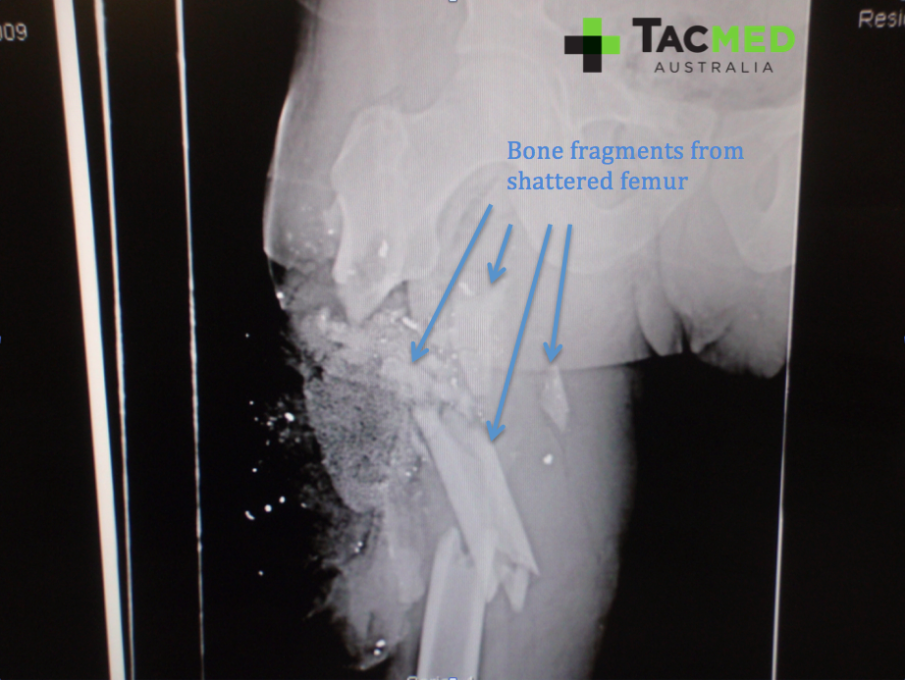

As with any limb injury, a high priority was to assess for blood flow distal to the wound in order to ascertain if the major blood vessels had been damaged. Remarkably, the casualty had normal blood flow to his feet, implying that the femoral artery was intact. Next came an X-ray to have a look at the underlying bone structures. The casualty had minimal movement in the leg at time of review, and we expected him to have a fracture of his femur underlying the injury. The following images of the X-ray highlight the main features, including the shattered femur from where the bullet struck, the bullet fragments from where the projectile had disintegrated on impact, and the granular material of the ACS.

Once the pins had been appropriately placed above and below the fracture site, the femur was pulled back out to its appropriate length and stabilized with external rods bolted onto the screws in the bones. The various pieces of shattered femur that can be seen in the X-ray images were all put back in their rightful place with the hope that they would heal back together as any other fractured bone does.